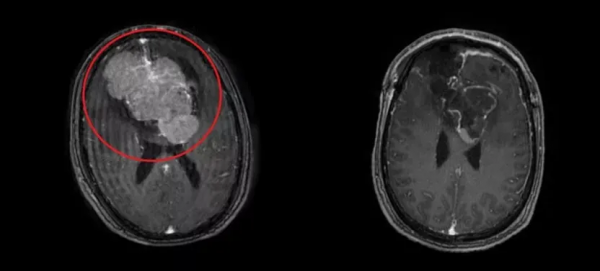

33歲的李小姐最近總是感到頭痛,並多次嘔吐。起初,她以為自己患上了產後焦慮症,沒想到去醫院檢查之後,竟然發現了一顆直徑近6釐米的顱內腫瘤。為尋求進一步治療,李小姐來到了南方醫科大學中醫西結合醫院,並在這裡接受了開顱手術。手術順利完成,李小姐恢復良好,而為他接診的醫生,正是有著“大腦‘拆彈’專家”之稱的神經外科醫生——陳陸馗。

經過檢查,陳陸馗在鍾叔腦中發現了一個大小9.3cm*7.3cm*5.3cm的巨大腦膜瘤。面對這一情況,陳陸馗帶領團隊進行充分討論,做了充足準備,最終與團隊經過10小時的手術,成功切除了鍾叔的顱內巨塊腫瘤。經過康復處理,鍾叔逐漸恢復正常,不再出現“老年痴呆”症狀,順利出院。